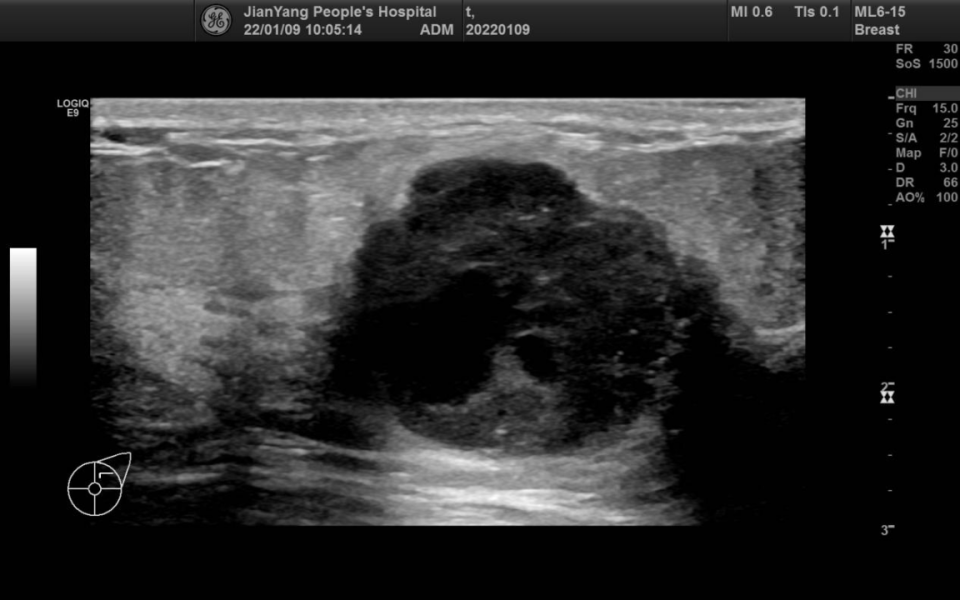

申请超声检查图像如下:

图片图 1 左乳 2 点钟方向肿物

两侧乳房切面形态轮廓正常,层次清楚,腺体回声不均匀,左乳 2 点钟方向距乳头约 20 mm 处可见范围约 28.3 mm x 22.4 mm x 28.1 mm 的低回声团,略呈分叶状,边界清楚,内可见不规则无回声区,其内可见较多条状血流信号。

双乳导管未见明显扩张征像。CDFI:余腺体内未见异常血流信号。

超声提示:左乳低回声团 BI-RADS 4A 类

MBC 多见于绝经后妇女,肿块较大,超声特征多表现为不均匀低回声,边缘光整,形态不规则,平行于皮肤,无钙化或微小钙化,后方回声无改变或增强,伴或不伴腋窝淋巴结转移,Adler 分级 Ⅱ~Ⅲ 级多见,阻力指数多>0.7。与间叶化生癌相比,鳞状细胞癌多表现为直径较大、呈囊实性回声、腋窝淋巴结无转移。